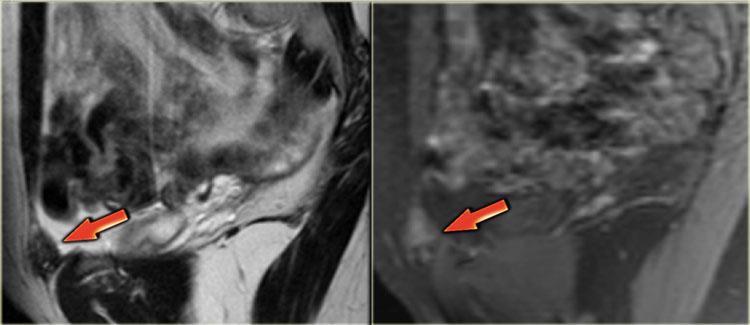

Hình ảnh T2W cho thấy lạc nội mạc tử cung xâm lấn thành bàng quang.

Hình ảnh T2W mặt phẳng đứng dọc cho thấy lạc nội mạc tử cung bàng quang xuyên toàn bộ chiều dày thành với tín hiệu đồng tín hiệu so với cơ và các ổ tăng tín hiệu, gợi ý các tuyến nội mạc tử cung giãn rộng.

Hình ảnh T1W kỹ thuật ức chế mỡ cho thấy các nang nhỏ tăng tín hiệu trong tổn thương do xuất huyết.

TRÁI: T2W mặt phẳng trán: buồng trứng áp sát nhau do dính. PHẢI: T1W+FS mặt phẳng trán minh họa các ổ xuất huyết nhỏ (mũi tên đỏ)

Hình ảnh T2W và T1W kỹ thuật ức chế mỡ bên trái cho thấy bệnh nhân lạc nội mạc tử cung có hai buồng trứng áp sát nhau (‘buồng trứng hôn nhau’), là kết quả của sự hình thành dính lan rộng.

Ở bệnh nhân này, một nang xuất huyết nhỏ của buồng trứng trái và một mảng nông xuất huyết cũng được ghi nhận (tăng tín hiệu trên T1, mũi tên đỏ).